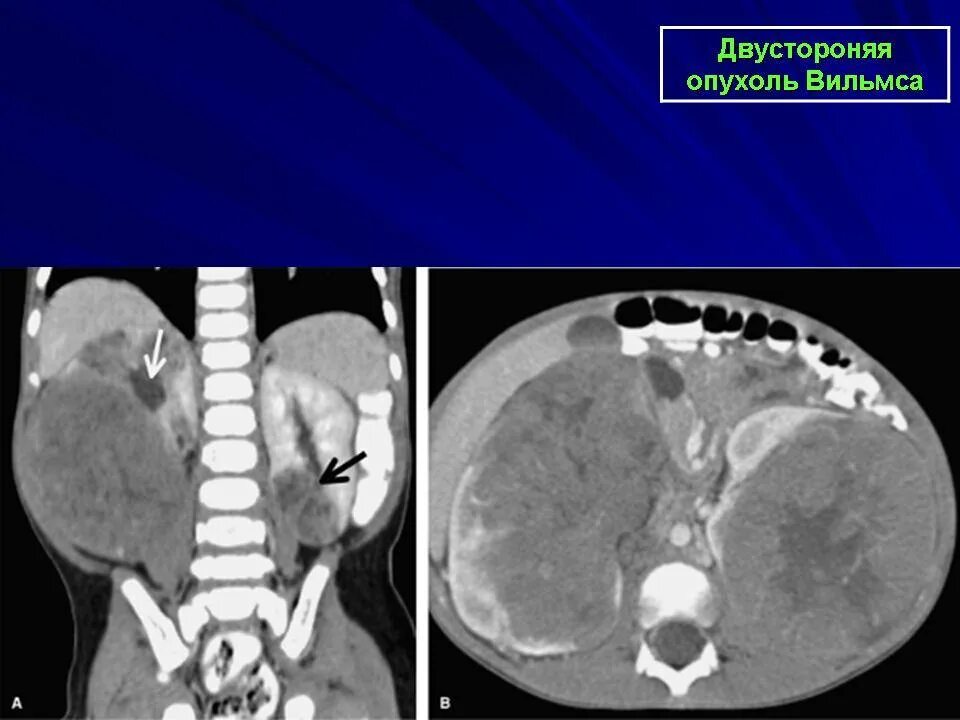

Почки 4 степени